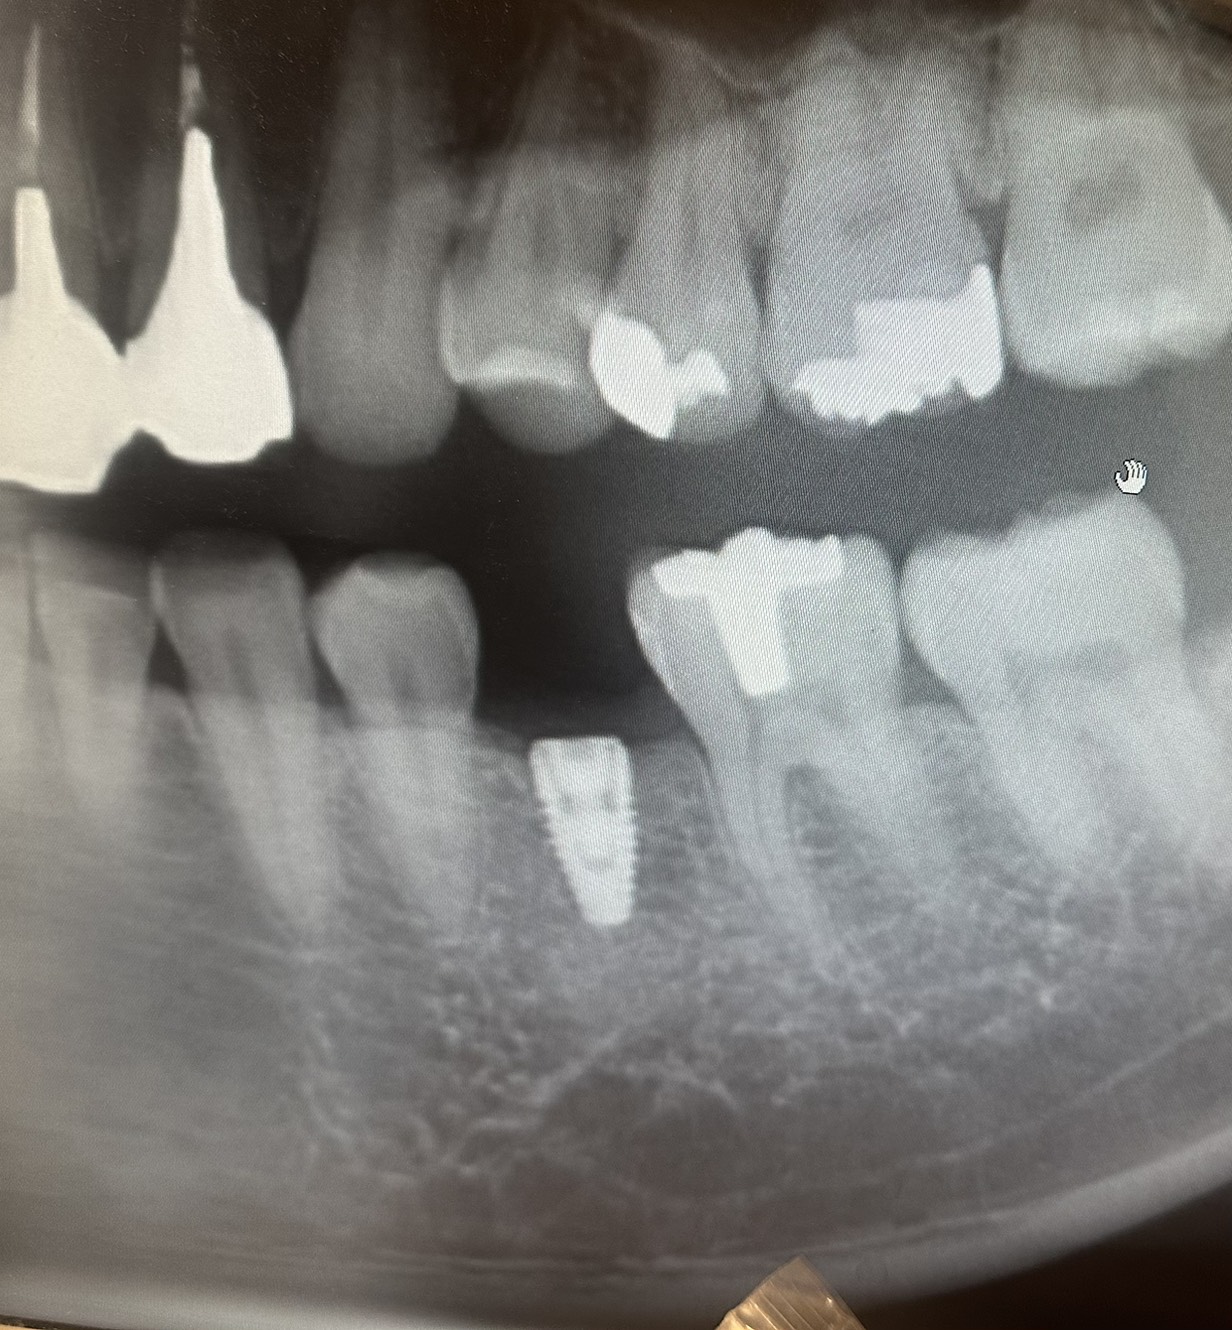

当院ではそのようなことがないよう初診時、治療開始前の説明を大事にしています。資料や写真、レントゲンを使って患者さまご自身にも出来る限りわかりやすくご説明させていただきます。

寿命を延ばしていく治療レントゲンやCT、口腔内写真、歯周ポケット検査など各種検査結果から、患者様一人ひとりに最適なむし歯・歯周病予防ケアをご提案します。

神経をできる限りとらず、

歯の寿命を延ばします歯がズキズキ痛い、ものすごい歯がしみるなどで「神経を取りましょう」と言われた経験がある方もいらっしゃると思います。しかし神経を取ると歯はかなり抜歯に近づきます。大きなむし歯でも神経を残せるケースも多くあります。的確な診断、高倍率の拡大鏡によりしっかり見える状態でむし歯のみを削り、むし歯以外の歯をできる限り削らず、適切な治療により歯の神経・血管をできる限り守ります。

治療の見える化

当クリニックが大切にしているのは、「10年後、20年後の患者様の将来」を見据えた治療です。お口の中は常に変化しているため、その歯を残すことが5年後や10年後に悪影響を及ぼす恐れがある場合は、今のうちの治療を検討する場合もあります。

最新のレントゲンや

CTなどによる検査 -